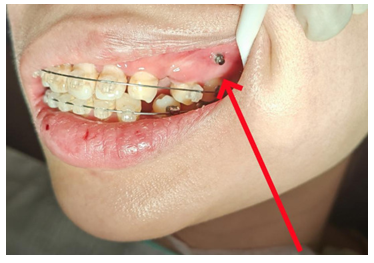

2、微创骨钉导航植入技术

采用CBCT三维定位结合口扫模型设计植入导板进行引导,避免微种植体植入时损伤牙根与神经,成功率大幅提升。